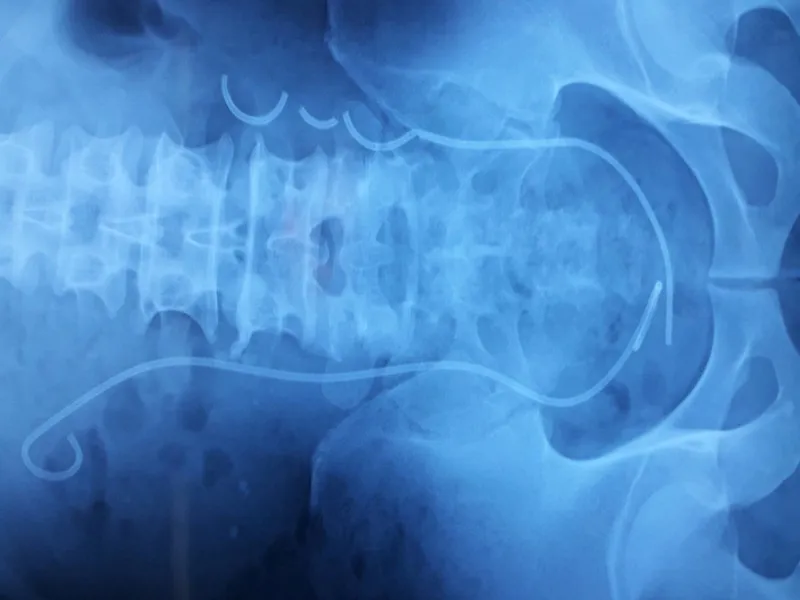

Hình ảnh X-Quang ống thông JJ đứt làm ba đoạn trong niệu quản bệnh nhận.

Qua kiểm tra, bác sĩ phát hiện bệnh nhân còn ống thông JJ bên trái bị đứt thành ba đoạn, trên thành ống thông bám nhiều sạn, nhất là ở hai đầu. Ngoài ra, bệnh nhân còn có một sỏi niệu quản bên phải khoảng 2 cm.